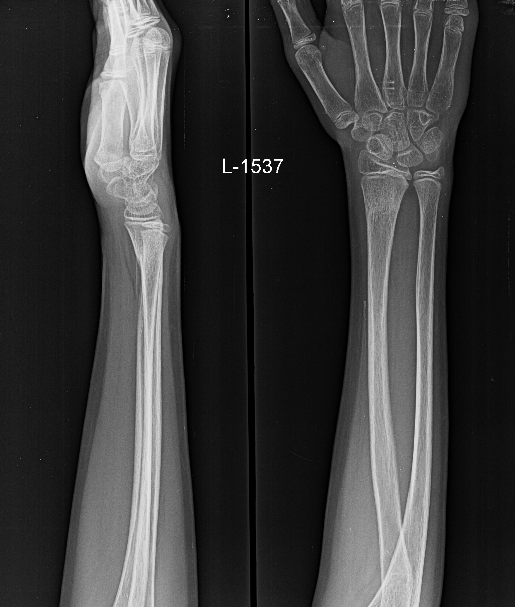

Frontal and lateral radiographs of the left forearm and wrist in an immature skeleton. Subtle buckling of the left distal radius lateral cortex without extension to the medial cortex or angulation, in keeping with torus fracture. There is associated anterior bowing of the pronator quadratus fat pad, consistent with deep soft tissue edema.

(NOTE: Read more on the pronator quadratus sign at https://radiopaedia.org/articles/pronator-quadratus-sign)